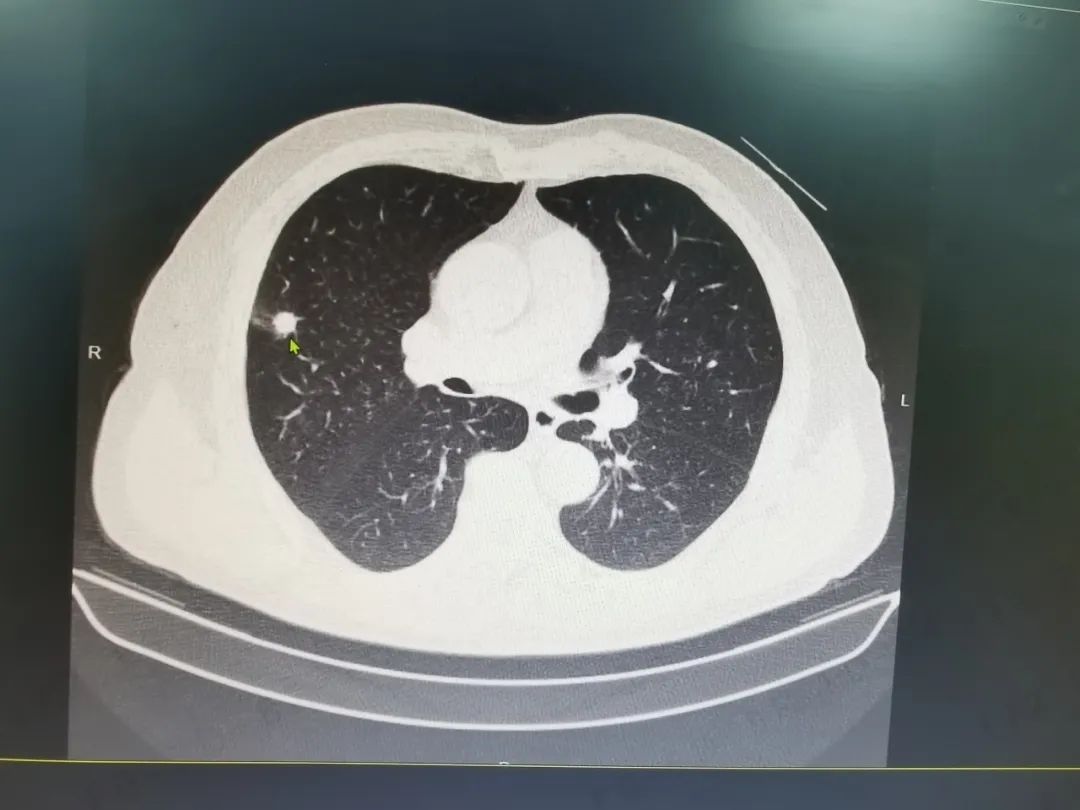

去年的这个时候,因为右上腹反复不适,程大爷就诊广济医院普外科,诊断“胆囊结石伴慢性胆囊炎”。行术前检查时,肺部影像意外发现肺部结节“病灶边界欠清,边缘不规则,高度怀疑是肺恶性肿瘤”。一番抽丝剥茧后,明确诊断程大爷的肺部结节系肿瘤原发病灶。手术指征明确后,代坤主任依托东方医院集团垂直管理优势,为老人邀请了集团胸心外科医疗中心高涛涛院长顺利为其行“单孔胸腔镜下肺癌根治术”。术后规范随访,大爷恢复良好。